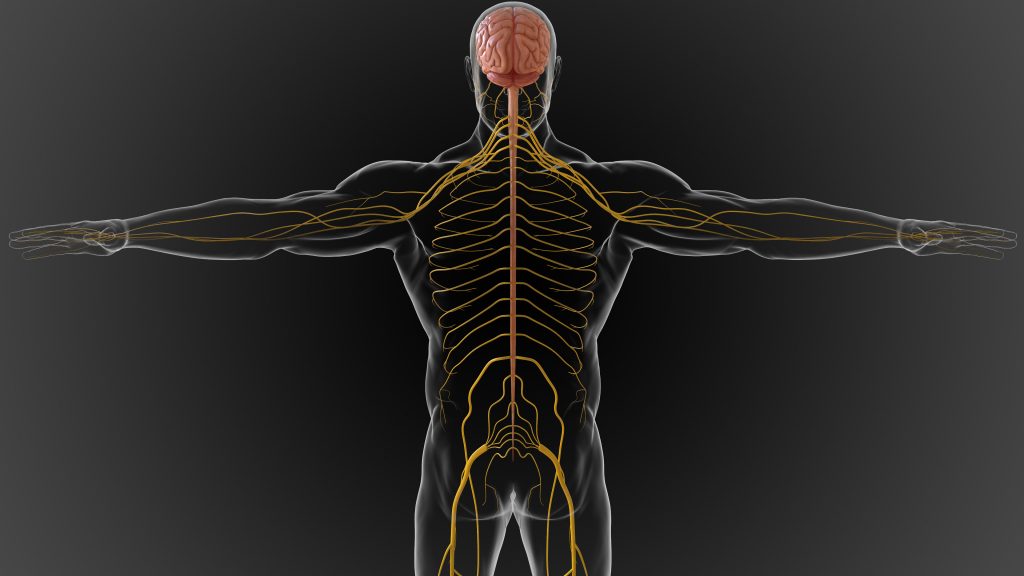

What do Peripheral Nerve Stimulators Treat Peripheral nerve stimulators are used to treat chronic nerve pain in the peripheral nervous system. The peripheral nervous system refers to all parts of the nervous system outside of the brain and spinal cord. Peripheral nerve pain can be caused by underlying conditions like fibromyalgia, diabetic regional pain syndrome, […]

Nerve pain, or neuropathic pain, is the result of either an injury, diet, toxins, or health condition that affects your nerves. Nerves throughout your body will send electrical signals to your brain that relay various sensations. The nervous system is bidirectional and the brain will send signals back to the extremities, organs, etc. Your nervous […]

Nerve pain, also known as neuropathic pain, is a type of chronic pain that results from damage or dysfunction of the nerves. There are several types of nerve pain, each with its own unique symptoms and causes. In this post, we will discuss 5 types of nerve pain: peripheral neuropathy, proximal neuropathy, autonomic neuropathy, cranial […]